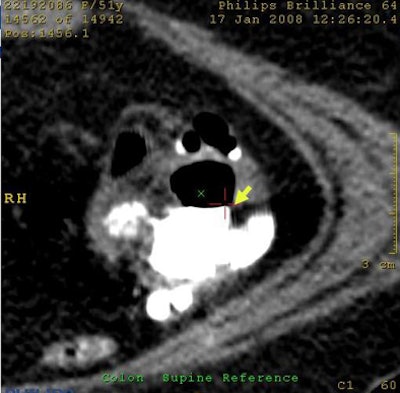

![]() |

| Electronic cleansing artifacts caused false positives resulting from untagged feces, pseudoenhancement of tagged materials (above), and air-contrast-wall interface (below). |